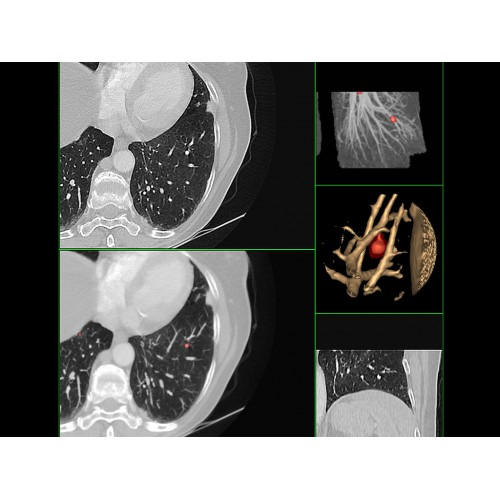

Онкология

• Раннее выявление новообразований и контроль эффективности лечения.

• Планирование лучевой терапии с высокой точностью.